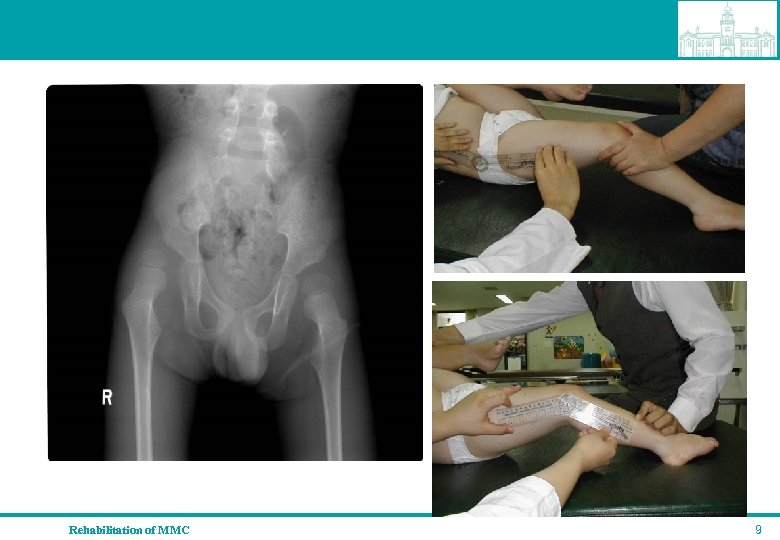

Clinical signs by spinal level L 1 -L 3 segments spared qhip flexion and adduction contracture, qearly paralytic hip dislocation, pelvic obliquity, qscoliosis, qgravity related equines deformity Rehabilitation of MMC 8

Rehabilitation of MMC 9

Clinical signs by spinal level L 4 -L 5 segments spared q hip abductor and extensor weakness q usually calcaneovarus foot deformity Rehabilitation of MMC 10